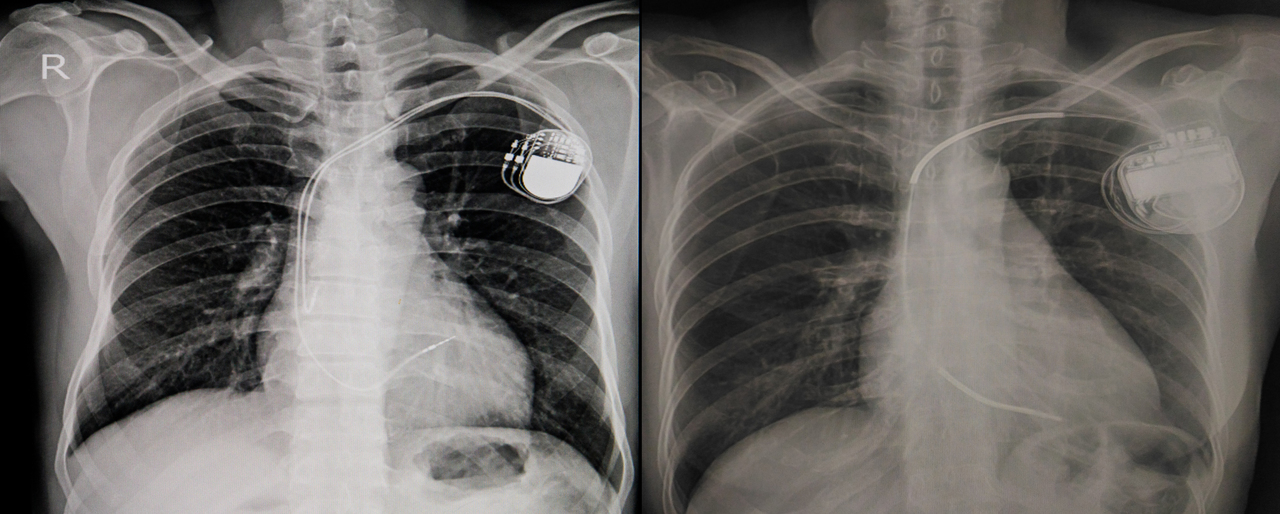

If you’re experiencing irregular and slow heartbeats, your doctor may recommend that you undergo minor surgery such as a permanent pacemaker insertion in the Philippines. From the term itself, a pacemaker regulates rhythm to help your heart beat at the correct pace. Upon surgery, this small battery-operated device is implanted in the chest to restore normal heart rates.

When this electrical pathway is disrupted, abnormal heart conditions occur, which is when a pacemaker becomes necessary. An implantable pacemaker mimics the natural electrical system of the heart and corrects slow electrical problems. It does so through its two parts:

- Pulse generator: This is a small metal container that holds a battery and a tiny computer. Electrical circuits regulate the rate of pulses sent to your heart.

- Leads (electrodes): One to three flexible, thin wires are each placed in a chamber (or chambers) of your heart to deliver the electrical pulses needed to adjust your heart rate.